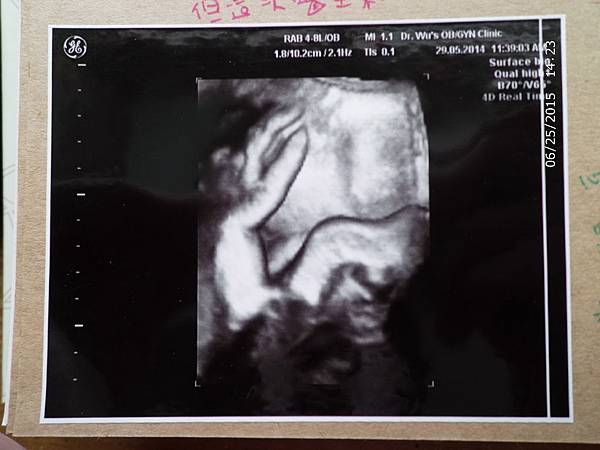

【孕期】超音波照片一定要這樣嗎......